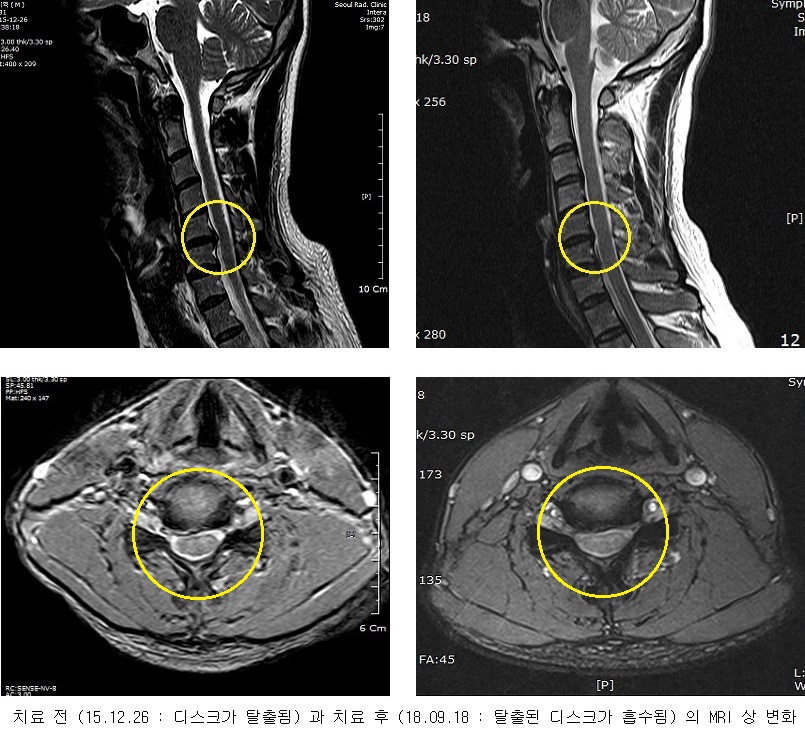

목이 심하게 욱신거리고 오른쪽 팔이 매우 저렸다.

2018-09-18